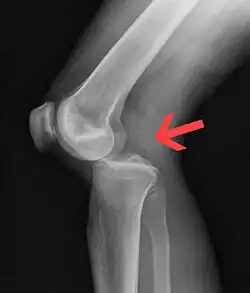

| Plain lateral X-ray of the left knee showing a posterior knee dislocation[1] | |

Plain X-rays, CT scan, ultrasonography, or MRI may help with the diagnosis.[2][11] Findings on X-ray that may be useful among those who have already reduced include a variable joint space, subluxation of the joint, or a Segond fracture.[5]